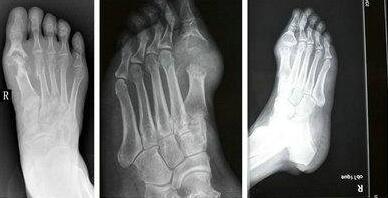

(图:张先生的脚关节已经开始变形,有明显浮肿)

经过详细的检查显示,化验:血尿酸:720 μmol/L,ALT:54,AST:43,肌酐值(肾功):71(59-104),抗“0” 定量检测(ASO):201.8。X线示:右足跖骨骨头处出现溶骨性缺损。根据检查结果,我院医生杜爱华为他制定了详细的治疗计划。

(图:三个疗程的治疗,张先生的脚步已恢复正常,浮肿消失)